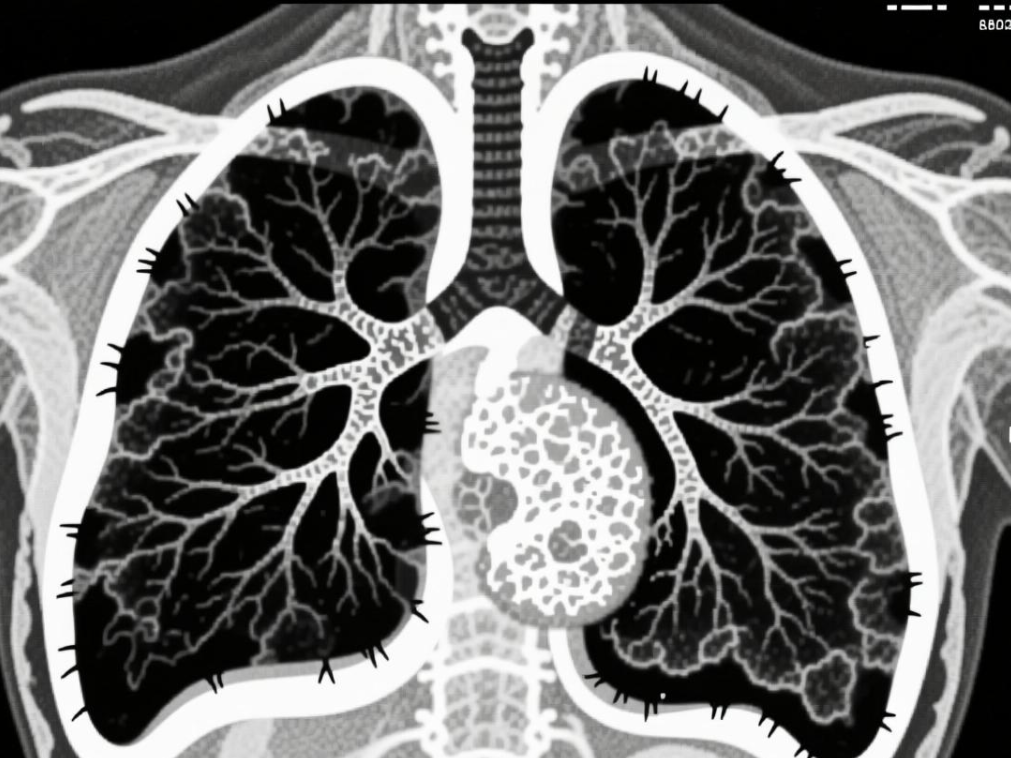

同样是肺癌,有人长期吸烟,有人从不碰烟,却走向了不同结局。肺鳞癌与肺腺癌,发病人群、症状和发现方式截然不同。真正决定生存率的,不是...[详情]

TAG标签:早期筛查 肺癌分型